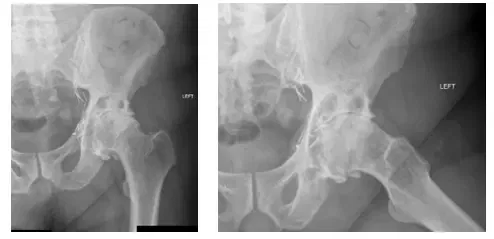

Las radiografías muestran artritis de las articulaciones de la cadera izquierda y derecha, con peores hallazgos en la articulación de la cadera derecha.

Tras la exploración y la revisión de las radiografías, se determinó que la paciente padecía una osteoartritis (OA) grave de la cadera izquierda. Se discutieron las opciones con el paciente, incluida una posible ATC izquierda. Se informó al paciente de que, aunque las radiografías indican una OA grave, la intervención quirúrgica aún no está indicada porque sólo experimenta dolor por la bursitis.

Las radiografías muestran una degeneración osteoartrítica de la cadera izquierda